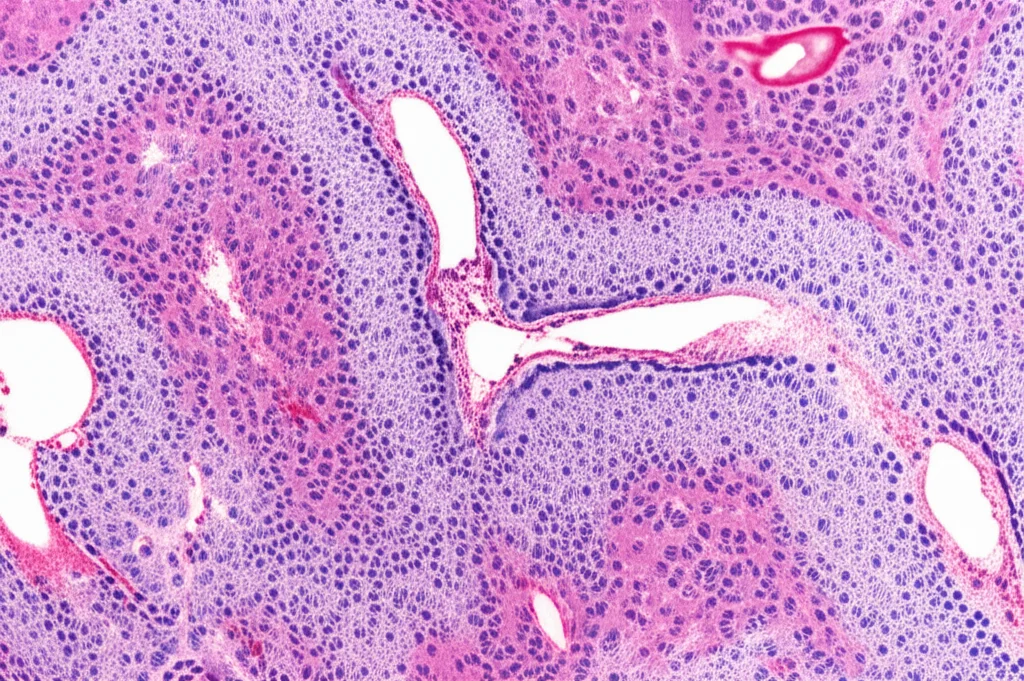

That’s where this study comes in, and honestly, it’s a game-changer. We’re talking about using some seriously clever tech – multiplex immunofluorescence, multispectral imaging, and advanced computer vision – to create detailed maps of where ILCs and their Th cell counterparts are hanging out in human lymphoid tissues. Not just a blurry overview, but a single-cell resolution map across whole tissue slides. It’s like finally getting that detailed street map of the immune city.

So, how did we pull this off? The core idea was to use a technique called multiplex immunofluorescence (mIF). This lets us stain for several different cell markers on the same tissue slice, using different fluorescent colors. Then, we used fancy scanners to capture multispectral images of the whole slide. But the real magic happens with the computer vision and analysis. We used software to identify individual cells based on their nuclei, figure out which markers each cell expressed, and then map their exact location (X-Y coordinates) on the tissue. This allowed us to calculate cell densities in different areas and, crucially, see who was hanging out near whom.

We looked at a bunch of different human lymphoid tissues: the thymus (where T cells grow up), lymph nodes and tonsils (key meeting spots for immune cells), the spleen (a major filter and immune hub), and parts of the gut-associated lymphoid tissue – the appendix and ileum (critical for mucosal immunity). We even looked at samples from patients with follicular lymphoma, a type of blood cancer that affects lymphoid tissue, to see how the immune neighborhood changes in disease. For each tissue type, we analyzed samples from multiple patients, giving us a robust dataset.

To identify the different ILC and Th subsets, we designed specific panels of markers. It’s a bit like giving each cell type a unique barcode based on the proteins they express. We had to be careful because ILCs can be a bit shifty, changing their look depending on where they are and what’s going on. We also made sure to exclude other cell types like B cells and conventional T cells so we were really focusing on the ILCs and Th cells. We even adjusted our approach for the thymus, including a marker (TdT) to distinguish immature T cells from ILCs, which turned out to be pretty insightful.